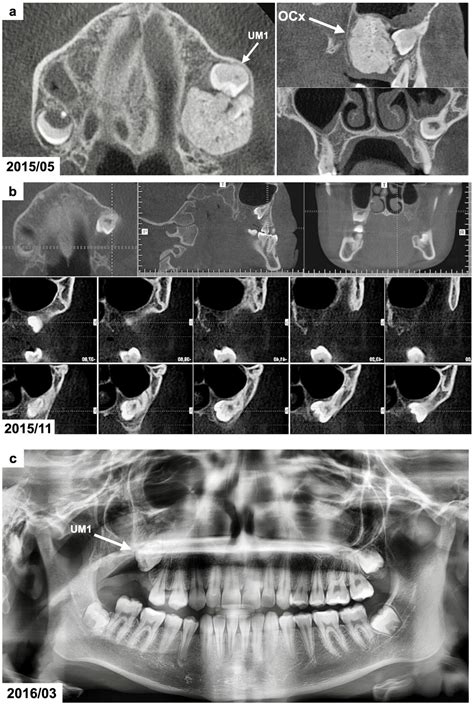

Combined Surgical and Orthodontic Treatment of Complex Odontoma in ...

mdpi.com